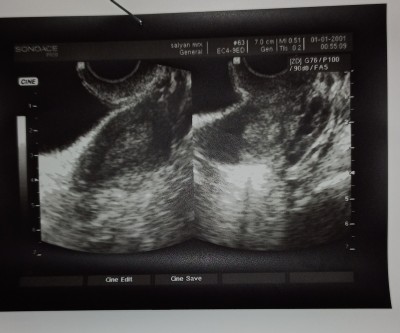

Kızlar bu gün doktora gittim vaginal birde üsten bakdı hamilelik gözükmüyor dedi. 2aydır regl olmuyorum + test 2 cizgi çıktı. Anlamdım((( 10 gün sonra tekrar gidicem. Geç döllenme ola bilir dedi. Çok heves etdim kızlar çok

Gebelik haftası 8